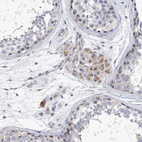

Immunohistochemical staining of human cerebral cortex, kidney, skin and testis using Anti-MPHOSPH10 antibody HPA035059 (A) shows similar protein distribution across tissues to independent antibody HPA035060 (B).